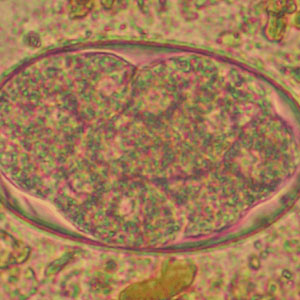

Les œufs des nématodes du genre Ancylostoma sont ovalaires avec des extrémités arrondies et larges et mesurent de 56 à 76 µm de long et de 36 à 40 µm de large. Ils possèdent une paroi fine et une morula peu dense avec 4 à 8 blastomères (Garcia, 2021). Ils sont indifférenciables des œufs de Necator americanus à l’examen coproscopique. De même l’ovodiagnostic ne permet pas à lui seul de déterminer l’espèce (Garcia, 2021).